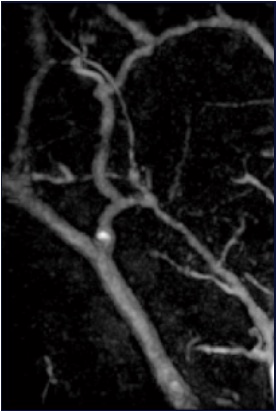

Photoacoustic tomography (PAT) uses diffusive optical illumination for the sample. The absorbers in the sample can then generate photoacoustic pulses. These pulses will be detected by the detector array. Using backpropagation image reconstruction, we can find the whereabouts of the absorbers inside the sample in 3D. We have performed photoacoustic tomography in both small animal imaging and clinical imaging. The image shows some human blood vessels imaged by the photoacoustic tomography system.